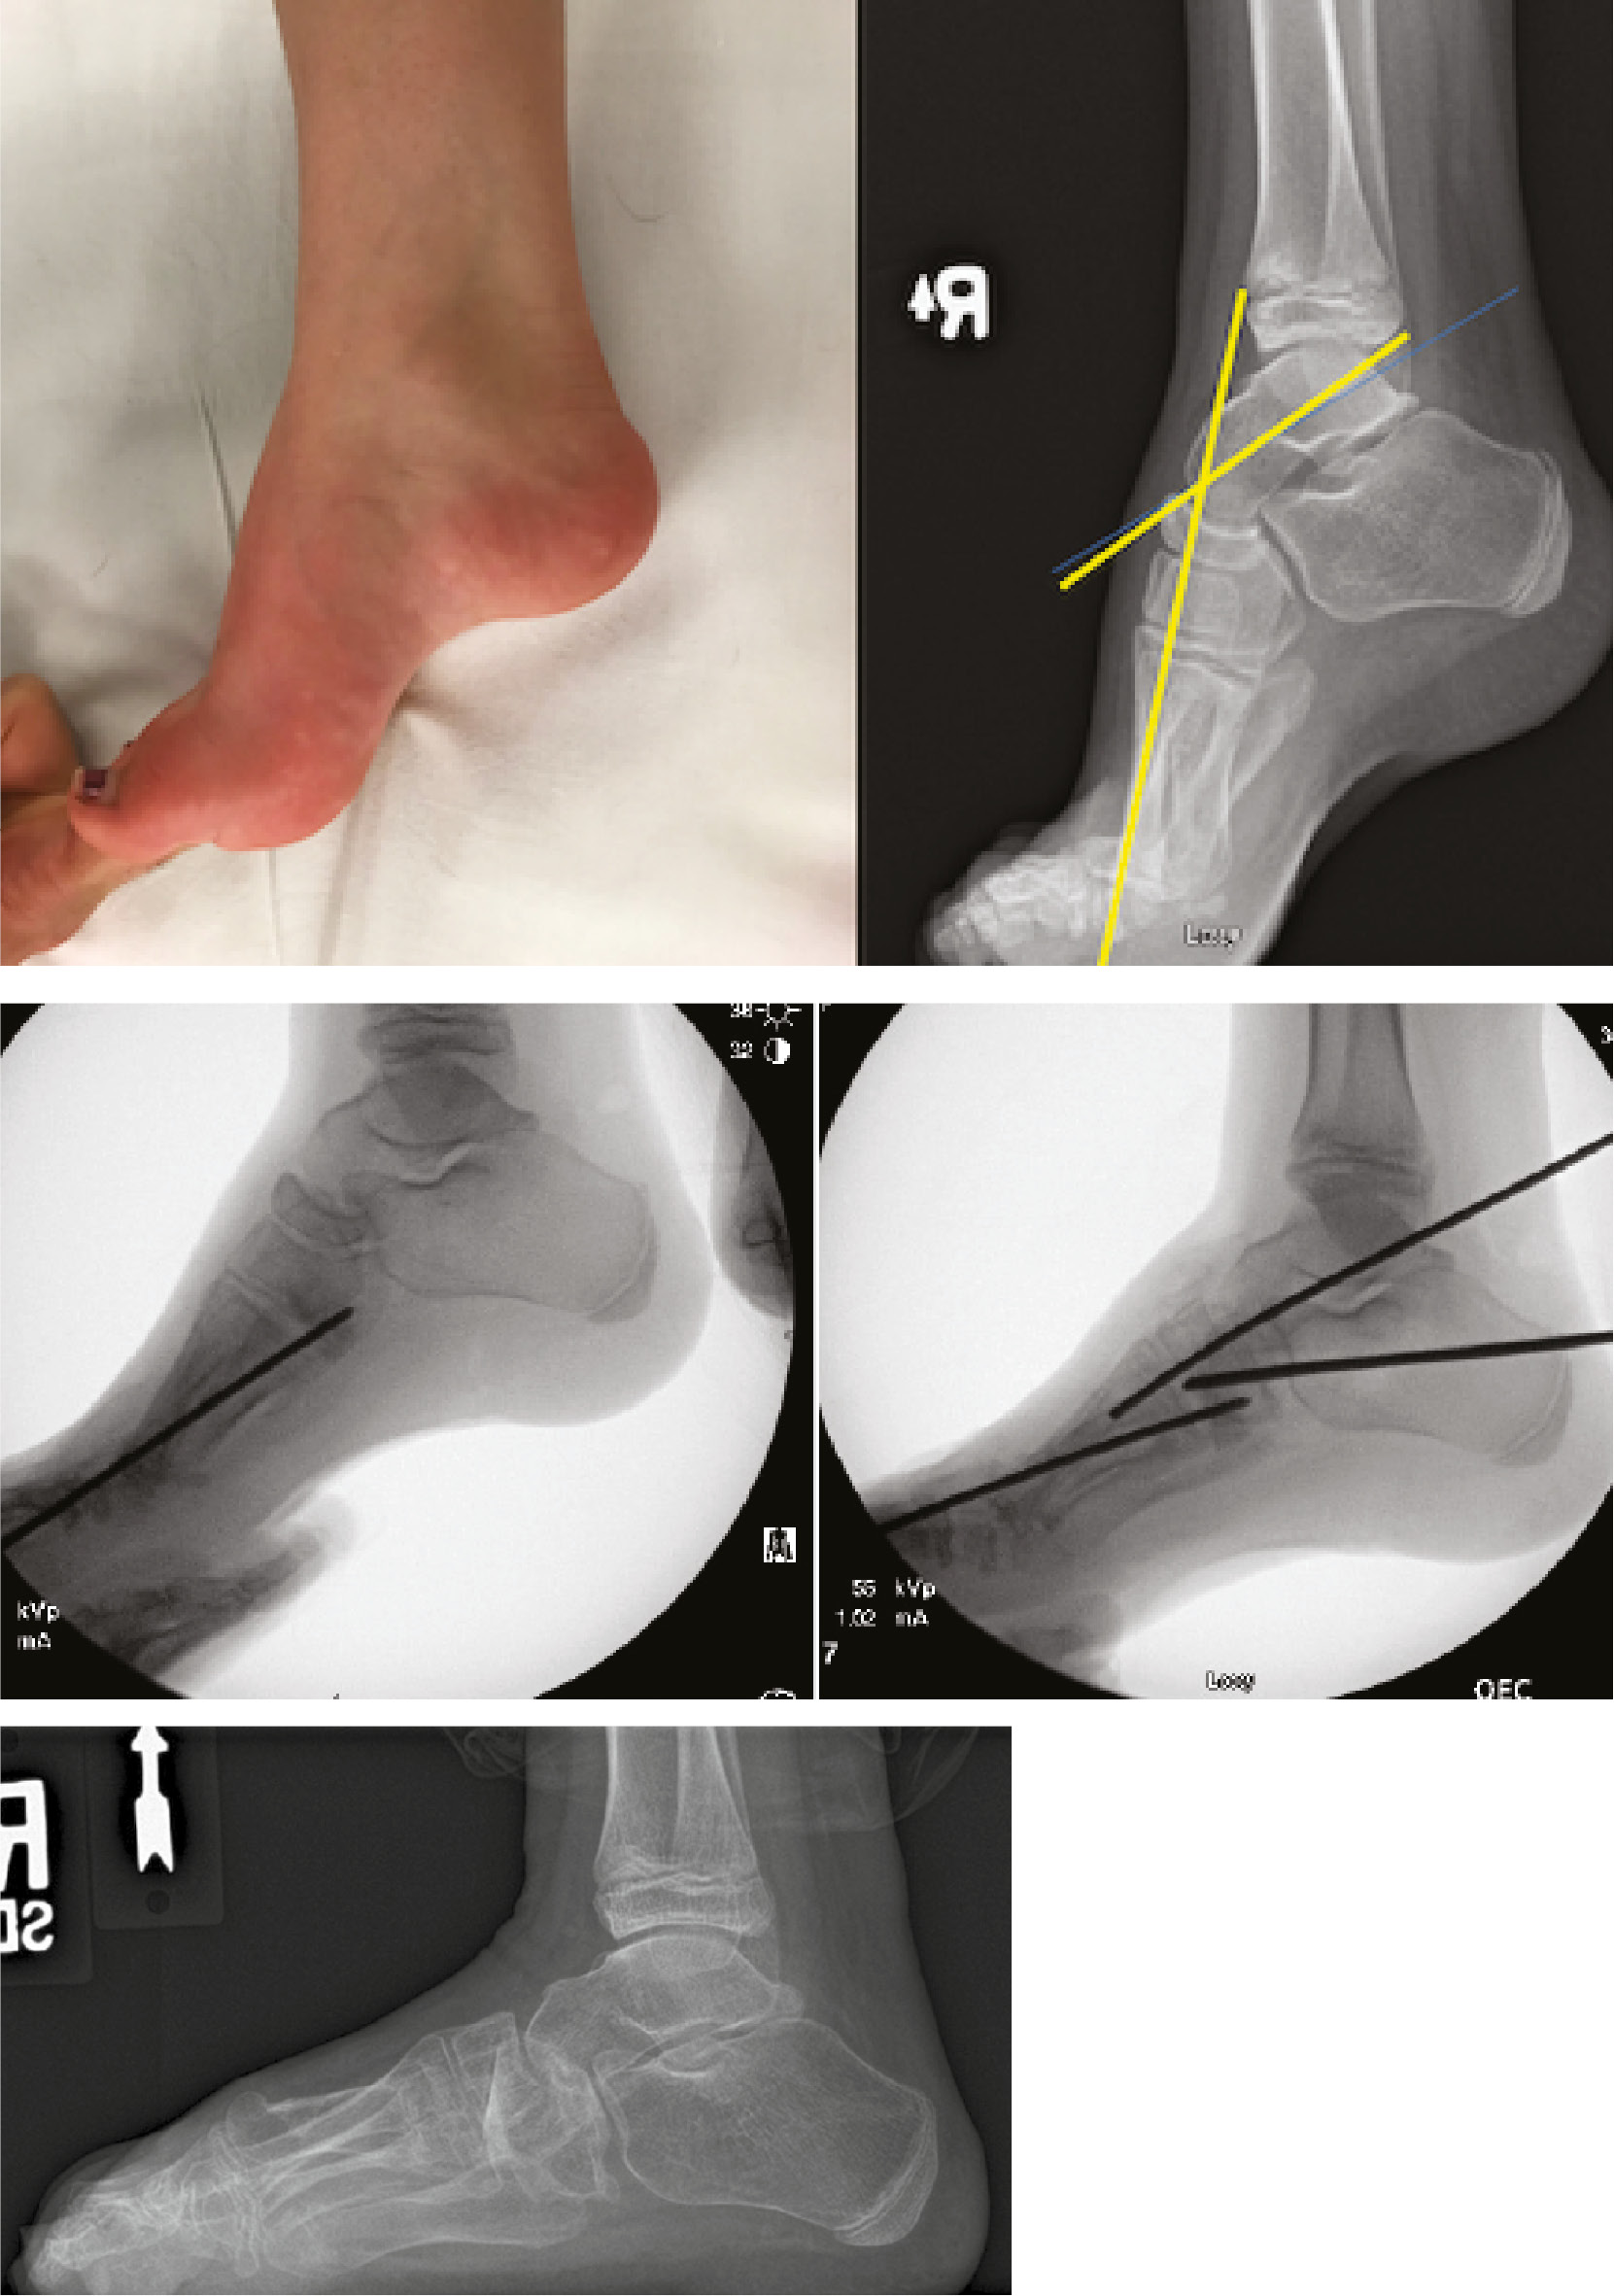

When Coleman block testing demonstrates a rigid hindfoot, the surgeon should perform a calcaneal osteotomy. This can be done in several ways, with most surgeons utilizing a lateral calcaneal slide osteotomy or Dwyer lateral closing wedge osteotomy, which serves to shorten the lateral column.42,50 This induces hindfoot valgus and secondarily centralizes the pull of the ankle dorsiflexors and plantarflexors across the hindfoot. In a recent study utilizing three-dimensional printed models of the hindfoot, performing a Dwyer osteotomy significantly improved hindfoot valgus angle, coronal calcaneal tilt, and lateralization of the weight-bearing surface, as opposed to oblique slide osteotomy.51 These radiographic parameters were even further improved when the Dwyer osteotomy was utilized to internally rotate the posterior calcaneal tuberosity fragment. Mubarak reported on the sequential application of metatarsal osteotomy, plantar opening wedge of the medial cuneiform and cuboid osteotomy, and calcaneal osteotomy with soft tissue procedures added as needed to address rigid hindfoot varus. They found that this stepwise approach to segmental deformity provided good to excellent outcomes and adequate correction of Meary and Hibb angles in a group of 20 feet.43 Wicart utilized a similar approach, performing plantar opening wedge osteotomy of the three cuneiform bones with the addition of a plantar release and Dwyer osteotomy when rigid hindfoot varus was present, averaging a cavus correction of 74% in a group of 36 feet.29 Calcaneal osteotomy is a very effective procedure when combined with the other procedures which are indicated to treat segmental deformity. This is supported by an older study by Lariviere et al. which found a very high cavus recurrence rate approaching 71% when Dwyer osteotomy was performed in isolation without the addition of midfoot osteotomies.52 When extensive bony reconstruction is required, the major goal of surgery is to avoid stiffness and prevent degenerative changes over time while also providing adequate pain relief and functioning. By addressing deformity during growth in this manner, with a careful application of procedures as they are indicated, a plantigrade foot can be maintained following skeletal maturity.